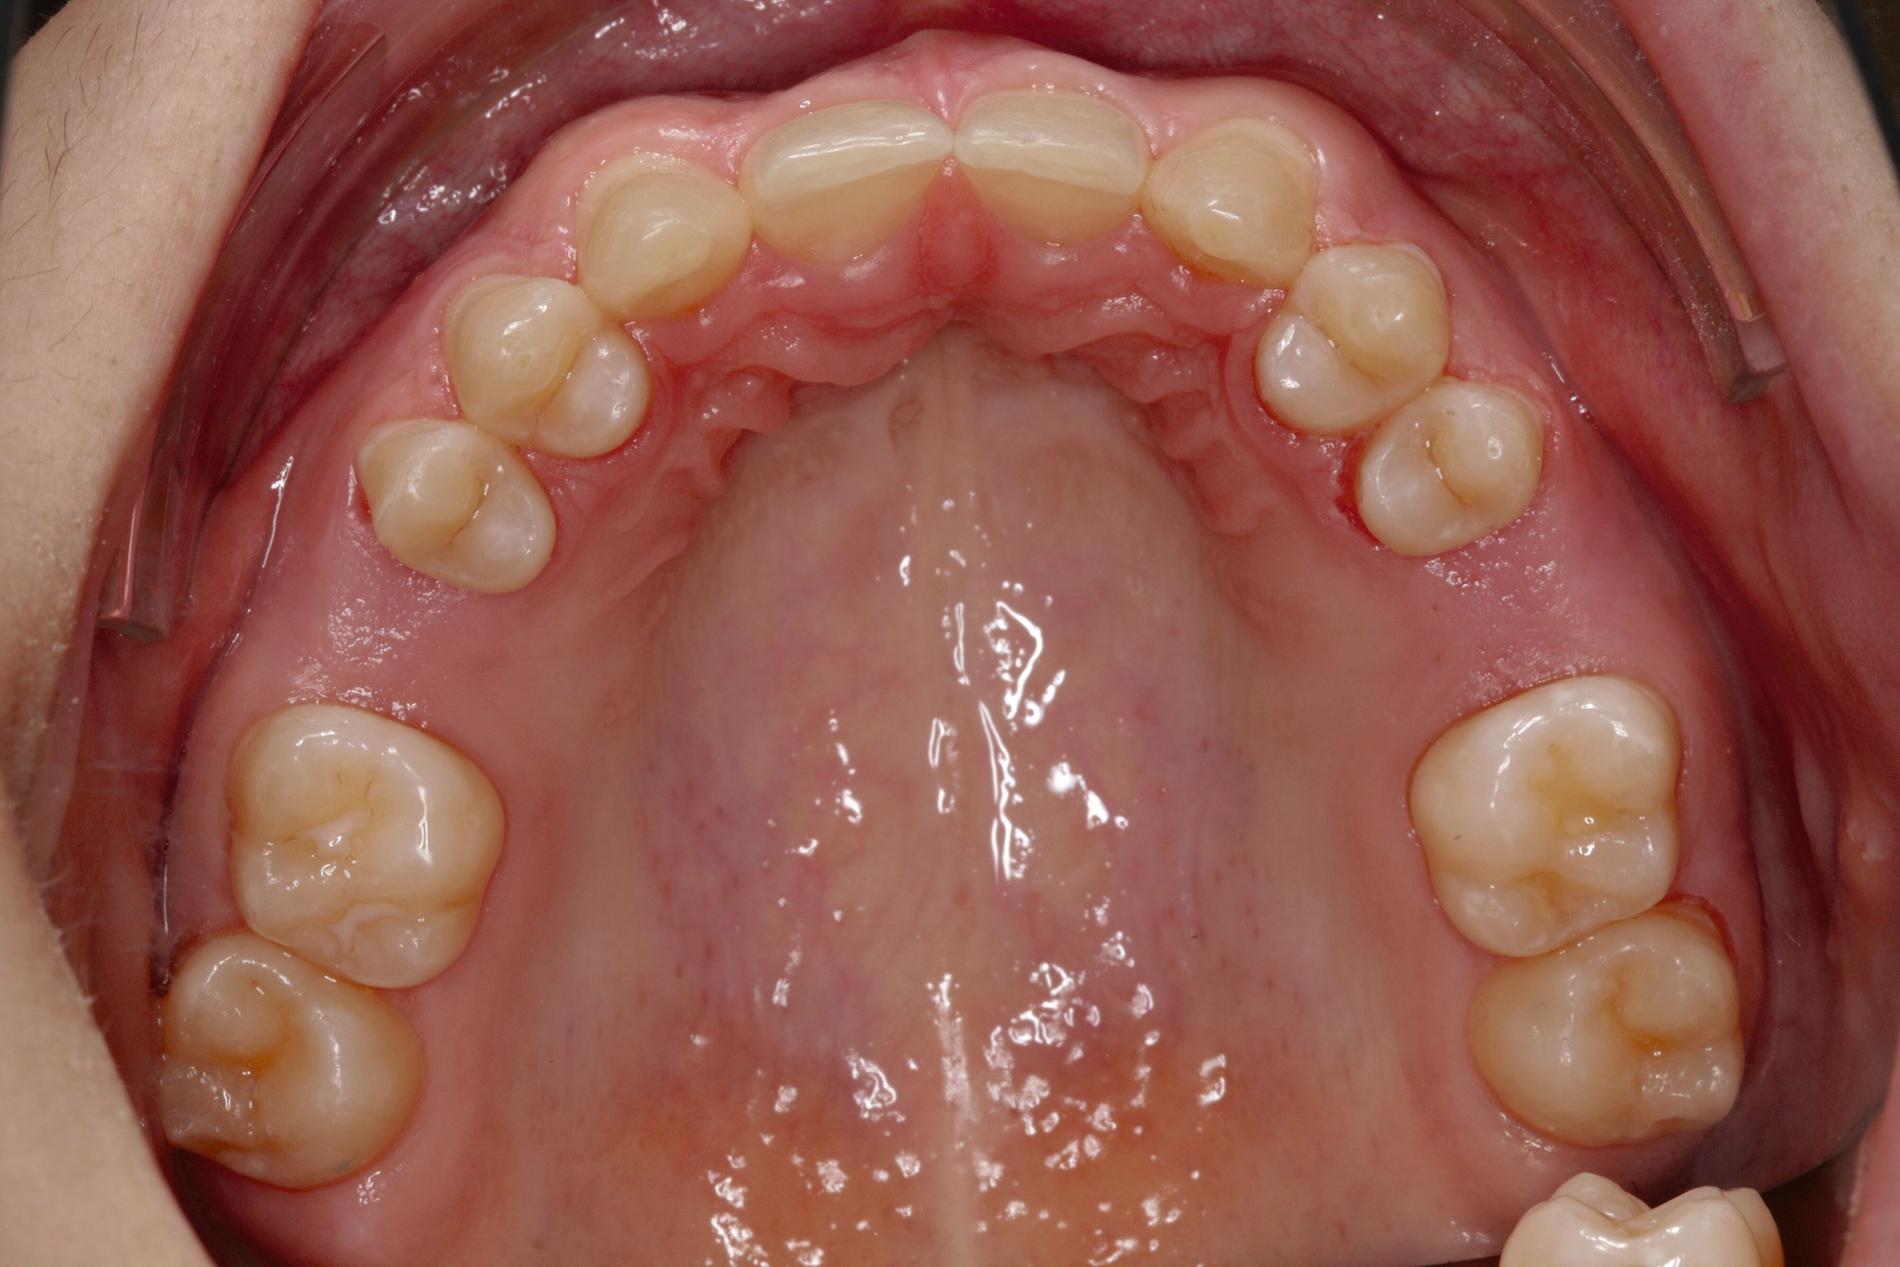

Bei dem gut zwölfjährigen Mädchen sind die seitlichen oberen Schneidezähne (Zähne 12 und 22) nicht angelegt. Zusätzlich zeigten sich verlagerte zweite obere Prämolaren.